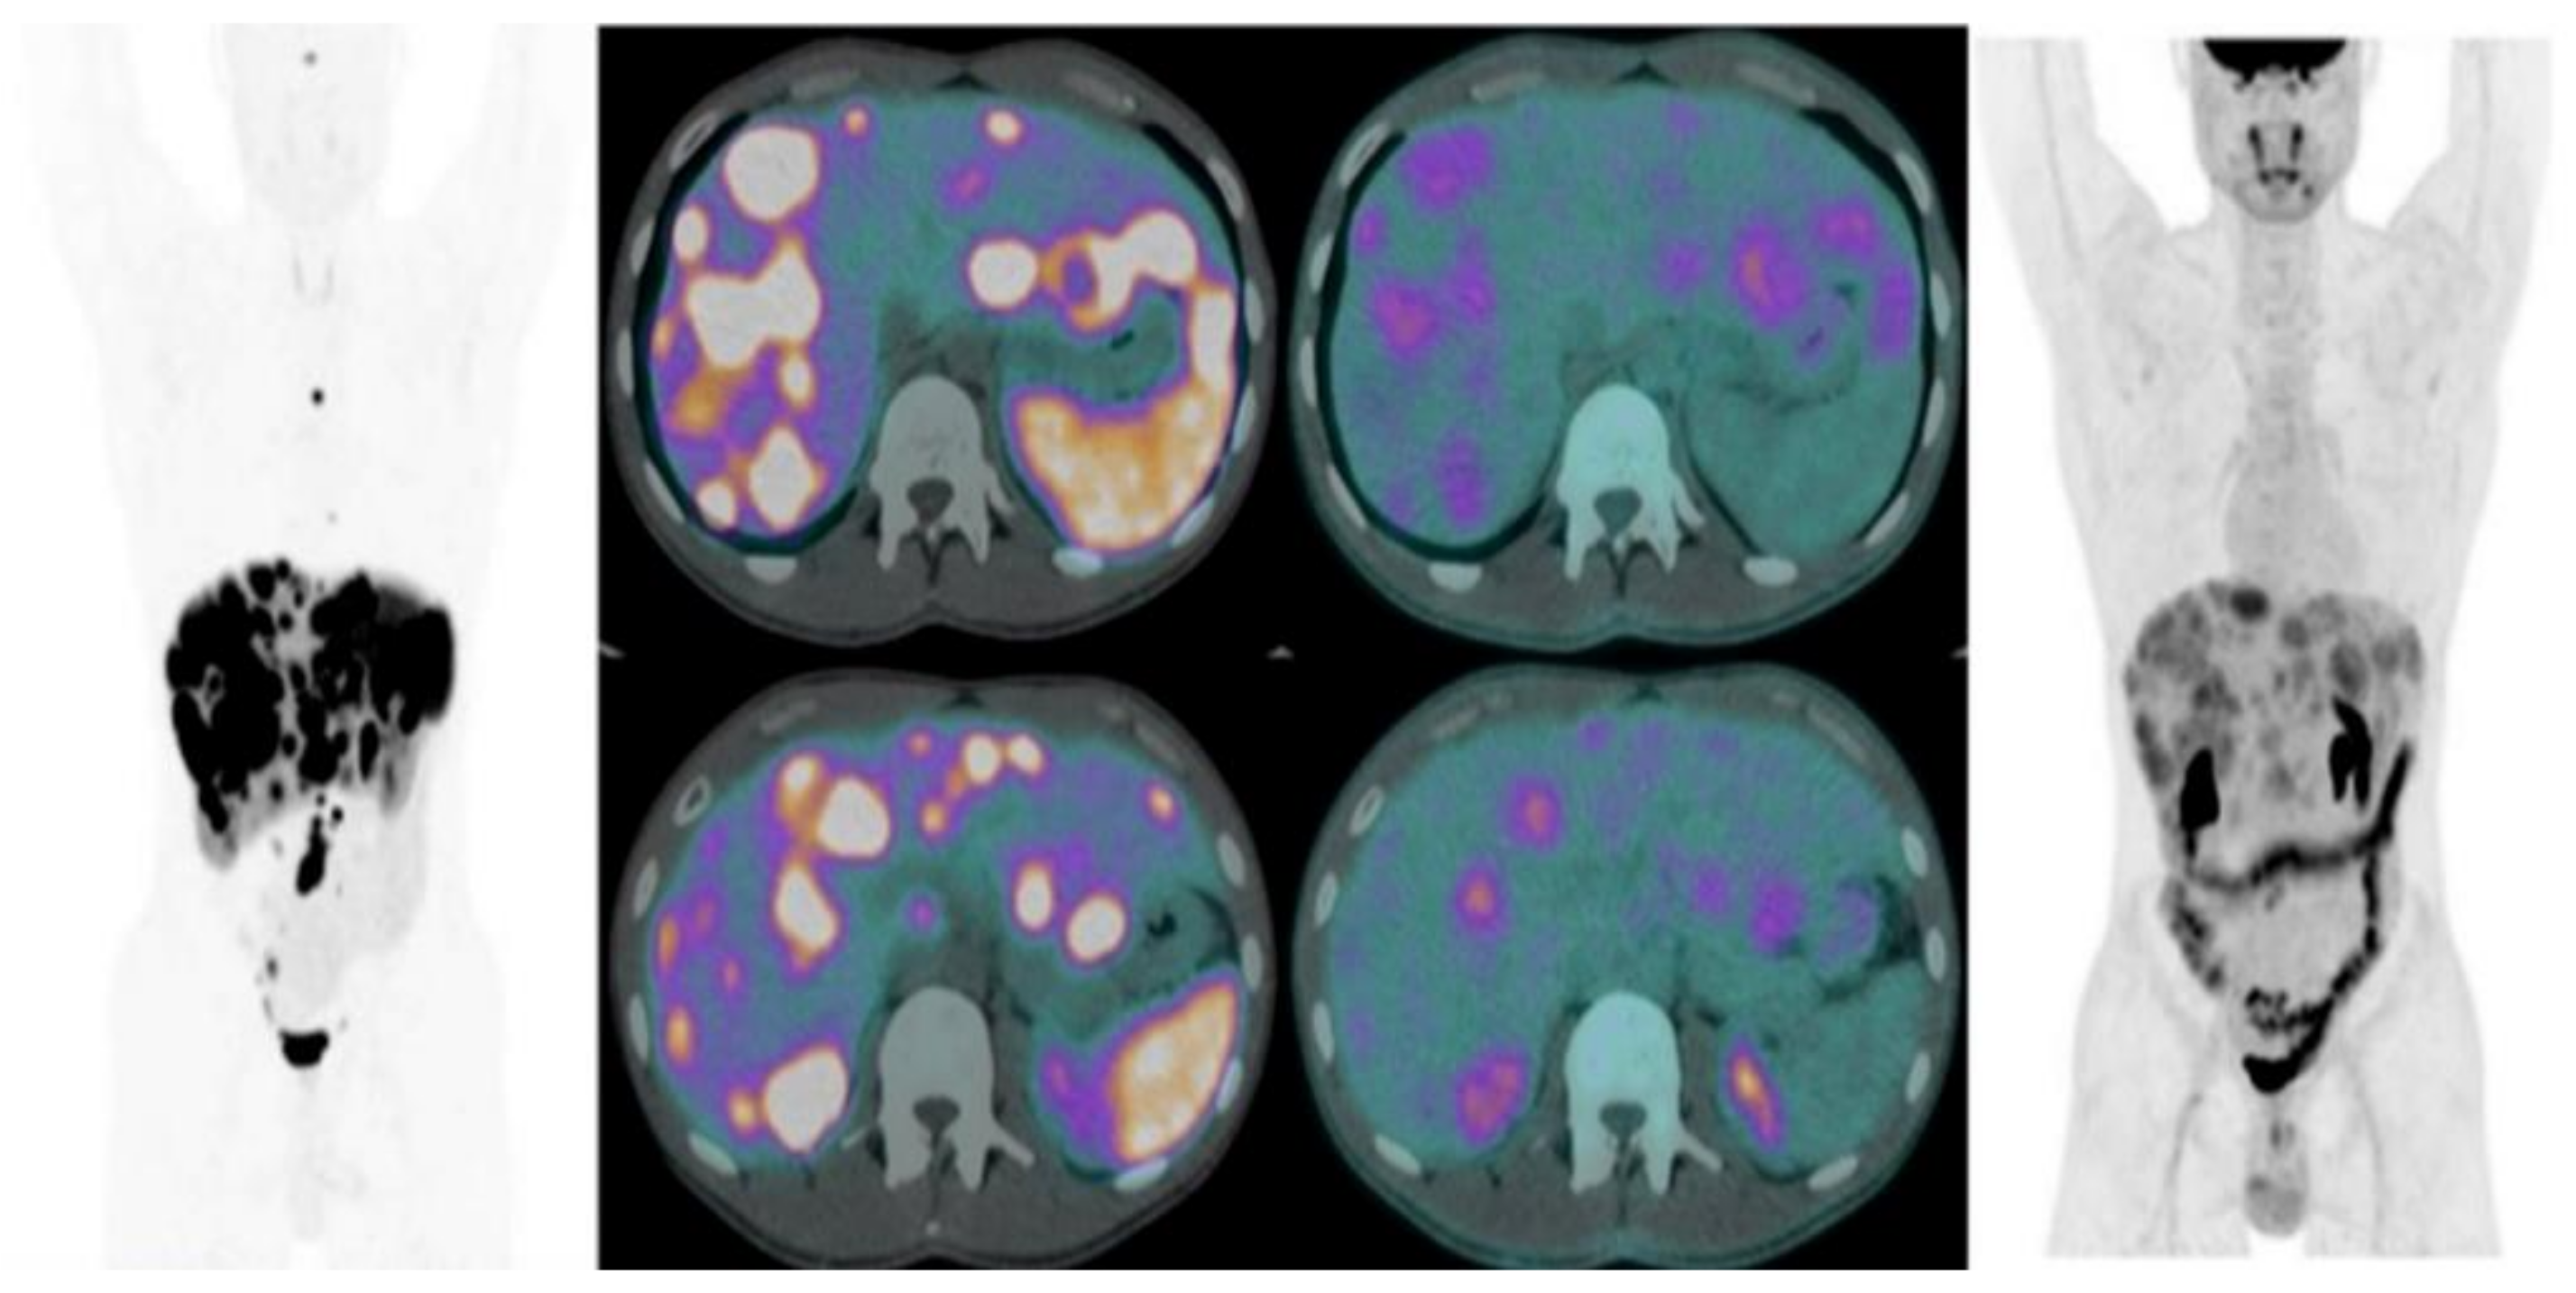

- Thapa, P.; Ranade, R.; Ostwal, V.; Shrikhande, S.V.; Goel, M.; Basu, S. Performance of 177Lu-DOTA-TATE-based peptide receptor radionuclide therapy in metastatic gastroenteropencreatic neuroendocrine tumor: A multiparametric response evaluation correlating with primary tumor site- tumor proliferation index and dual tracer imaging characteristics. Nucl. Med. Commun. 2016, 37, 1030–1037. [Google Scholar] [PubMed]

- Zhang, J.; Liu, Q.; Singh, A.; Schuchardt, C.; Kulkarni, H.R.; Baum, R.P. Prognostic value of 18F-FDG PET/CT in a large cohort of patients with advanced metastatic neuroendocrine neoplasms treated with peptide receptor radionuclide therapy. J. Nucl. Med. 2020, 61, 1560–1569. [Google Scholar] [CrossRef] [PubMed]

- Sansovini, M.; Severi, S.; Ianniello, A.; Nicolini, S.; Fantini, L.; Mezzenga, E.; Paganelli, G.; Severi, S.; Ianniello, A. Long-term follow-up and role of FDG PET in advanced pancreatic neuroendocrine patients treated with 177Lu-D OTATATE. Eur. J. Nucl. Med. Mol. Imaging 2017, 44, 490–499. [Google Scholar] [CrossRef]

- Alevroudis, E.; Spei, M.E.; Chatziioannou, S.N.; Tsoli, M.; Wallin, G.; Kaltsas, G.; Daskalakis, K. Clinical Utility of 18F-FDG PET in Neuroendocrine Tumors Prior to Peptide Receptor Radionuclide Therapy: A Systematic Review and Meta-Analysis. Cancers 2021, 13, 1813. [Google Scholar] [CrossRef]

- Ambrosini, V.; Kunikowska, J.; Baudin, E.; Bodei, L.; Bouvier, C.; Capdevila, J.; Yao, J. Consensus on Molecular Imaging and Theranostics in Neuroendocrine Neoplasms. Eur. J. Cancer 2021, 146, 56–73. [Google Scholar] [CrossRef]